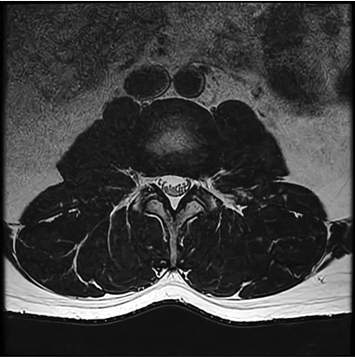

Conventional

384 x 256 (4 NEX)

3:00 minIAI (Innovative AI)

384 x 256 (2 NEX)

1:29 minscan time reduced up to 50%